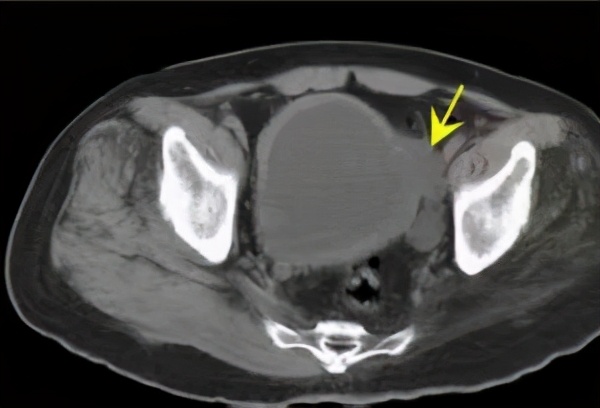

上图所示:63岁男患,有脑出血术后病史,长期卧床,近期存在小便*禁失**。CT尿路造影检查示膀胱壁增厚,存在膀胱憩室,伴有双肾积水,双侧输尿管扩张。考虑存在神经源性膀胱可能